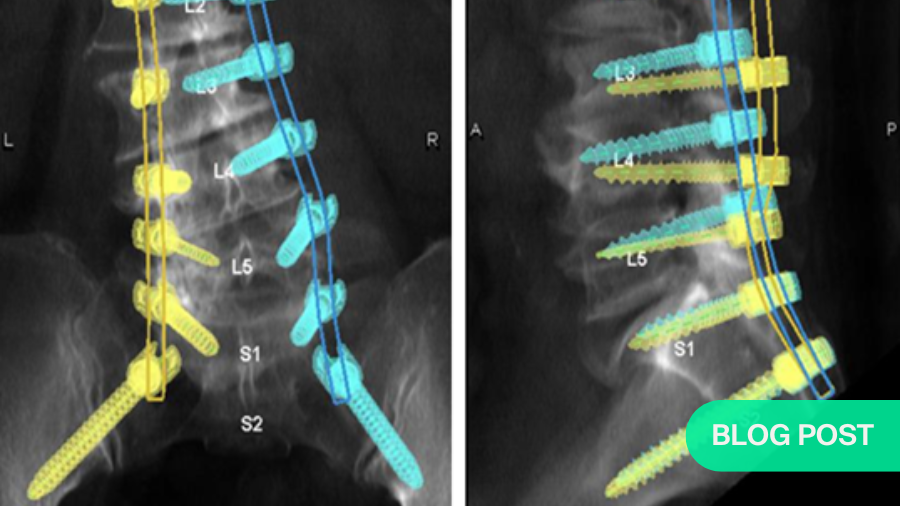

The most common use of the robots in spine surgery is for placement of the pedicle screws. The surgical planning of the pedicle screws (starting point, trajectory, length, diameter) is performed pre-operatively using the CT scan of the patient by the robotic software.

Intra-operatively, the robot is either attached to the operating table (i.e.) table-mount or floor mount at one end of the patient. A navigation tracking camera is placed at the other end to track the position of the patient and the navigated instruments/ implants during screw insertion.

The robotic software then performs a ‘3-D scan’ to register the position of the patient in space. Using an image intensifier, fluoroscopy images of the area of interest are then obtained. Matching of the bone windows of the CT scan stored in robotic software with these fluoroscopic images is performed. This is a critical step that enables the robotic software to configure and understand the bony anatomy of the patient (placed in a prone/ lateral position for a pedicle screw fixation).

This is followed by the registration of all the surgical instruments (bone awl, pedicle finder, and bone tap) and implants to the navigation software.

Once all these steps are completed, the operating technician aligns the robotic arm to the required position over the surgical site (based on the commands of the surgeon) and guides the trajectory for the insertion of pedicle screws.